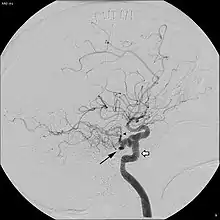

In around 0.1 to 0.6% of individuals, as sampled by magnetic resonance angiography, the trigeminal artery fails to involute and remains in the adult brain, in a condition called persistent trigeminal artery.[3] This condition is more common in women than in men, with approximately 1.8 times as many women having the condition.[6] Knowledge of a persistent trigeminal artery may be important in certain brain surgeries, as the condition is rare and an accidental cut to the artery could lead to hemorrhage.[1] Although the discovery of a persistent trigeminal artery is sometimes an incidental finding, its presence is also associated with various pathological conditions, and must therefore be considered carefully when diagnosing these conditions.[7]